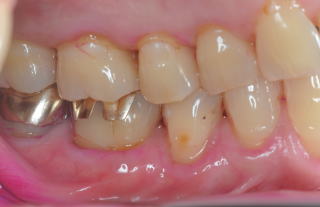

患者:83歳、女性

医療面接:子宮癌(全摘)、卵巣全摘、狭心症(1997年)、白内障手術(RL)(2009年)。帯状疱疹(体幹部、肋間神経支配部)(2010年)は当Clinicで治療。M.K.(胃癌)部分(1/2)開腹手術(2014年)。M.K.手術前の周術前口腔ケアでは、大学病院口腔外科受診時、担当医が口腔状態の良好状態に驚愕されたようだ。現在も毎月のS.P.T.(Supportive

Periodontal Therapy)を継続中。

(図15)2015年7月27日、83歳。高年齢と残存歯数ばかりが問題視されているが、歯槽骨の状態、歯肉、Pocketの状態を含めた歯周病を評価すべきである

歯周病治療38年経過:83歳(女性)残存歯数28本